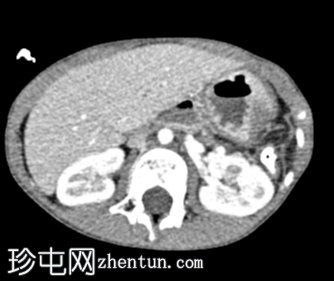

斜位

消化道造影检查显示食管口径正常,胃明显延长,延伸至盆腔区域。

左胸腔可见囊性透亮区,与腹部相连,导致心脏轮廓向右侧移位。